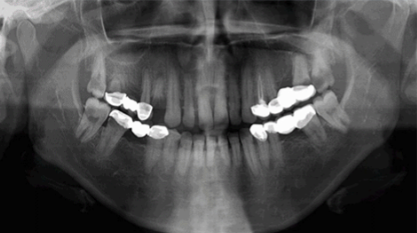

VELMENI for Dentists® 2D

VELMENI is as easy to use as it is powerful. Scan 2D radiographs to increase detection accuracy by 30%. FDA cleared for 2D Panoramic, Bitewing and Periapical X-Rays.